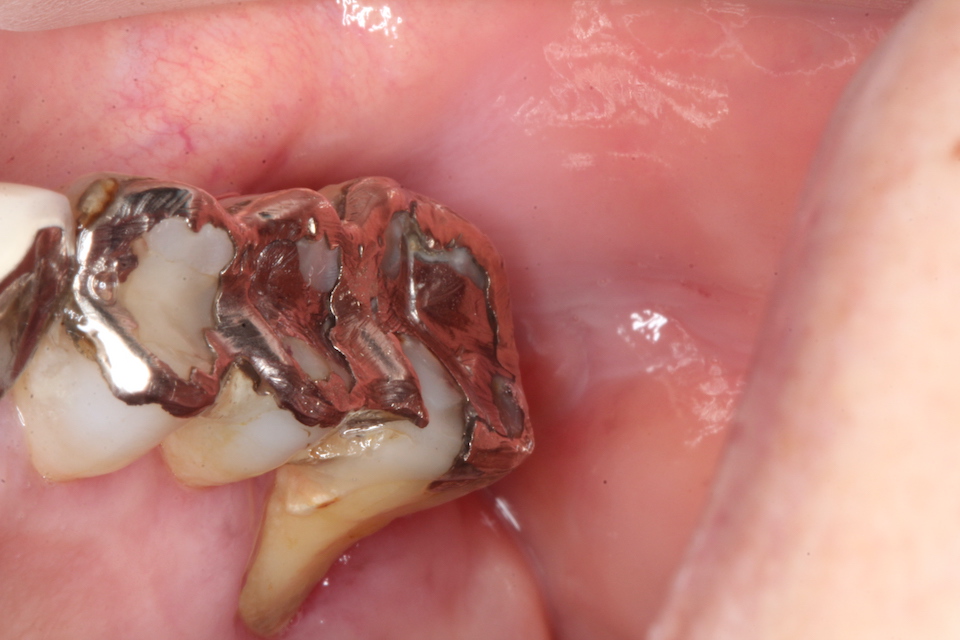

CRで漏洩しないようにカバーして終わり。これで痛みや強烈な沁みは消失する。こんな簡単なことで歯髄炎が治るとか信じられないかもしれないが、これが事実だ。冠を被せるまで何度も患者を通わせるなどという患者を苦しめる必要はない